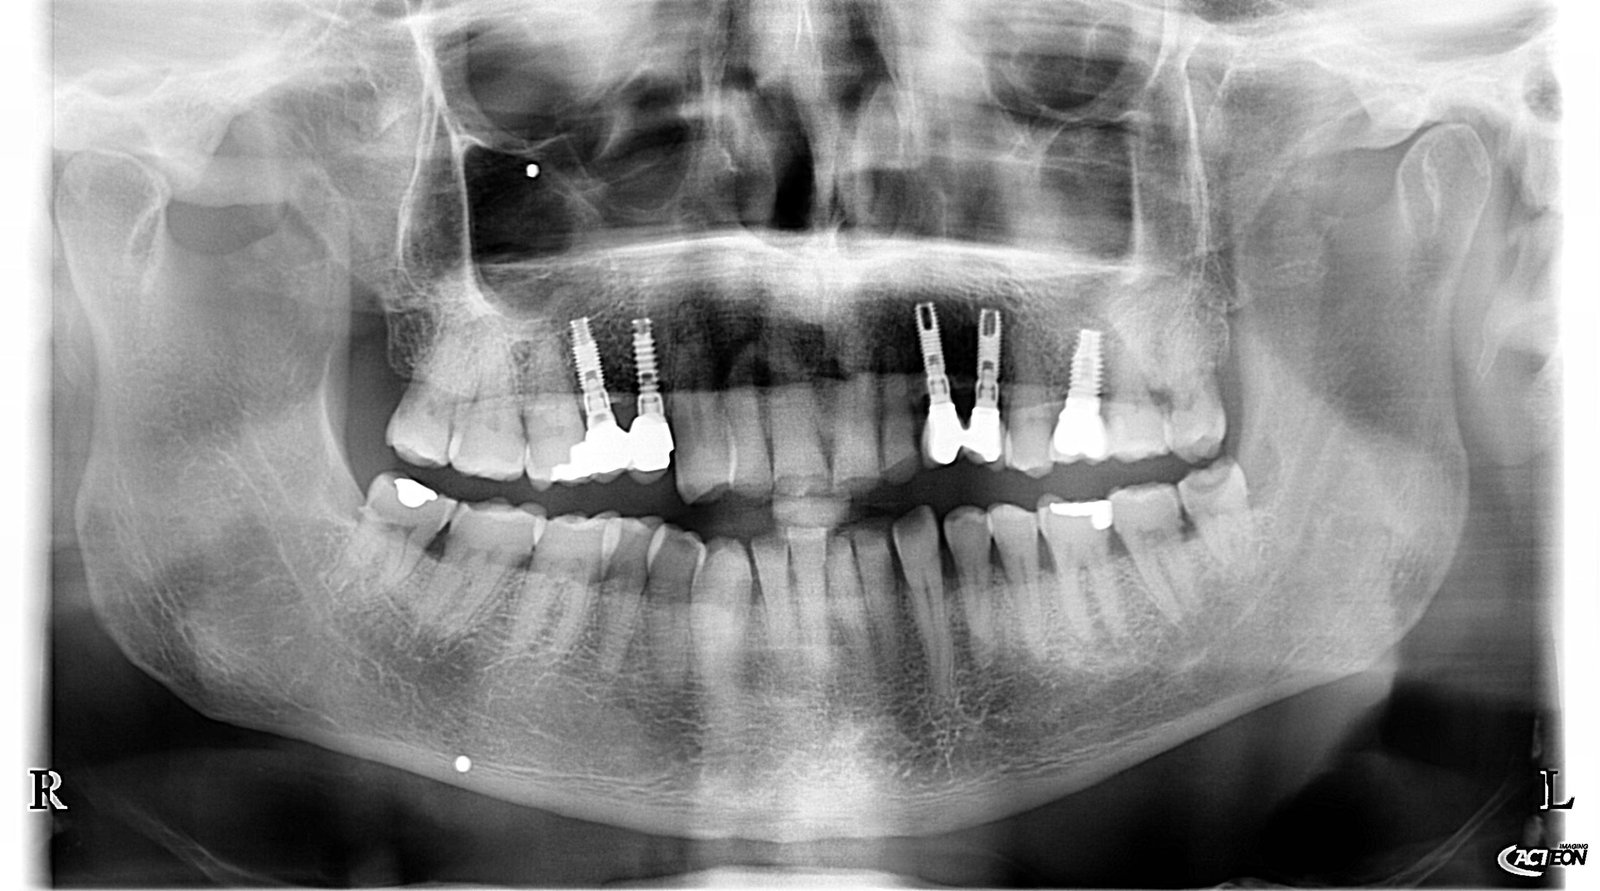

Buenos días compañeros. Necesitaría ayuda para identificar la marca de los implantes que lleva esta paciente, parece que son todos iguales. Se los colocaron sobre el año 2.000, pero no [...]